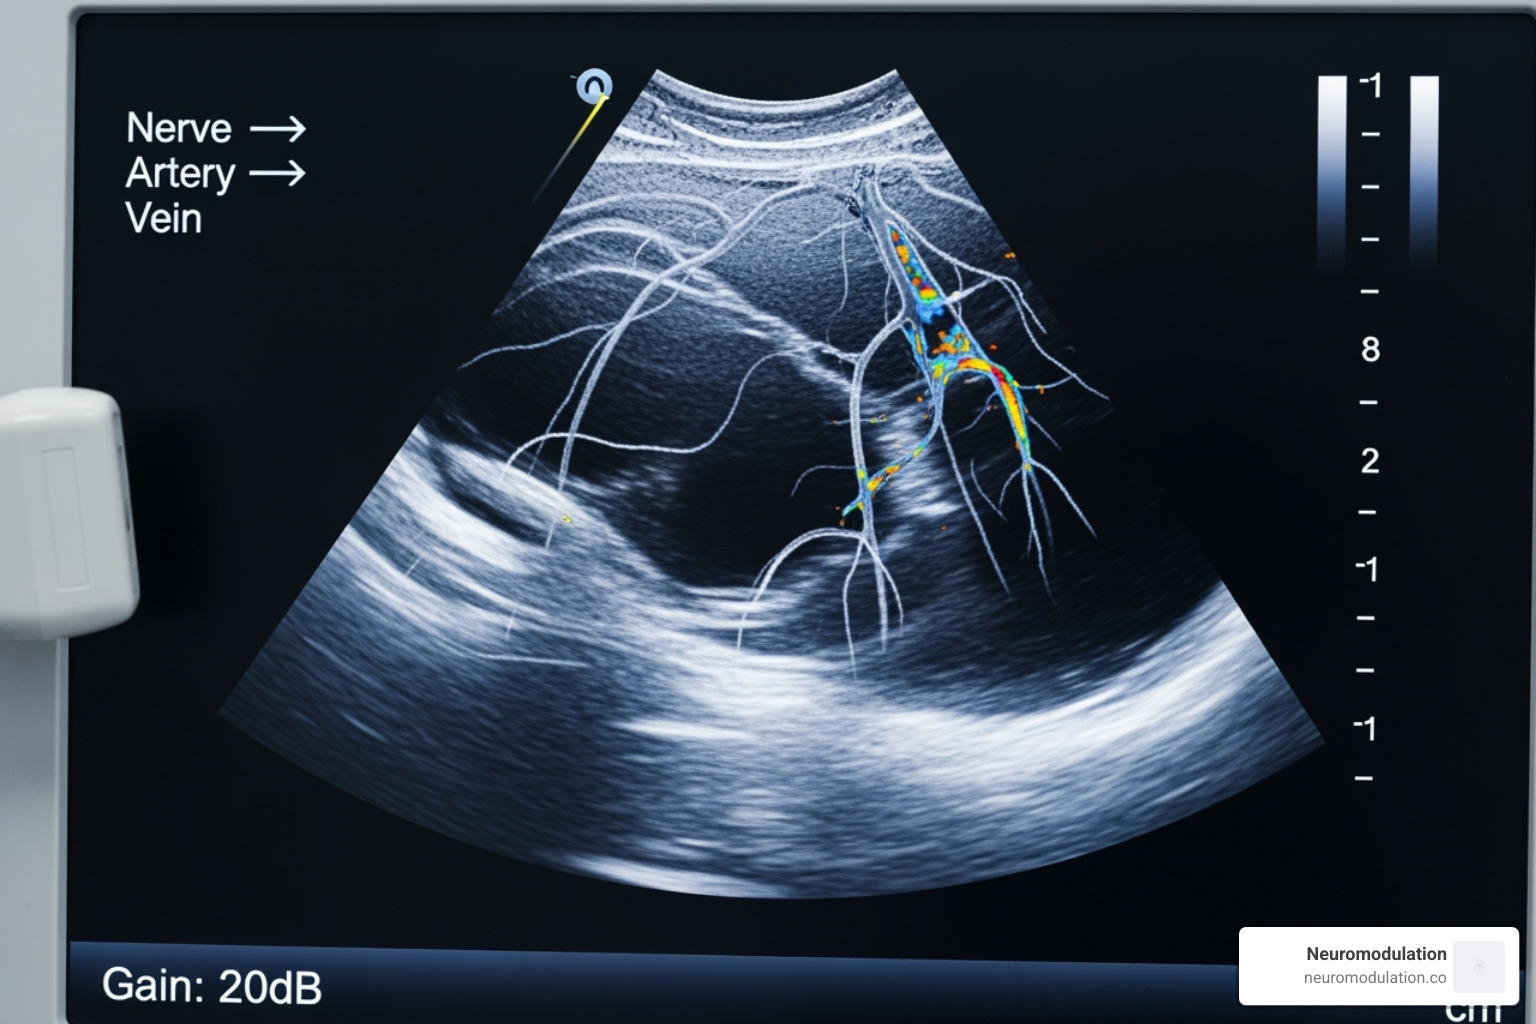

Ultrasound guidance is the foundation of modern regional anesthesia, and you’ll become an expert at it. Programs from Stanford to Sunnybrook emphasize mastering ultrasound-guided techniques. You’ll learn to visualize nerves clearly, watch your needle placement in real-time, and see exactly where your local anesthetic spreads. Some programs, like Frank H. Netter MD School of Medicine, use ultrasound exclusively for all peripheral blocks. While ultrasound is king, programs like Toronto Western also teach nerve stimulation techniques to give you a complete skill set.